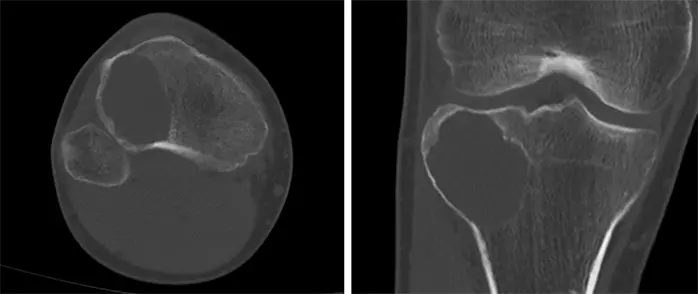

画像所見

受診時の膝関節X線画像では,右脛骨の骨幹端から骨端に及ぶ骨透亮像が認められ(Figure 1),単純CTで,同様に膨張性に発育する44x40x37mmの溶骨性病変が認められ,関節面まで1mm程度のところまで進展している.硬化縁はなく,内部は筋肉より低濃度で石灰化は認められない(Figure 2).また,右膝関節のMRIでも右脛骨近位外側,骨幹端から骨端線を越えて骨端まで及ぶ44×40×36mm大の病変を認める.内部はT1強調像で低信号,T2強調像で筋肉より高信号でほぼ均一.周囲に軽度の骨髄浮腫を伴い,拡散強調像では高信号を呈している.脂肪抑制T1強調像で高信号であるが,造影後との差分画像で全体が増強されている.以上の所見よりGCTが疑われる(Figure 3).